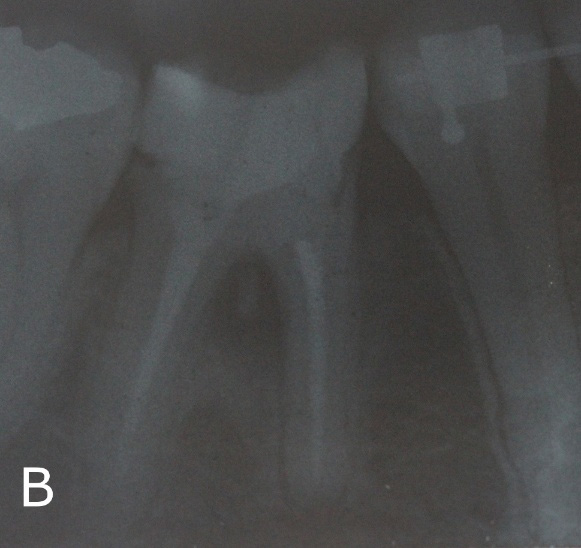

Patient, 28 years, male, attended to the dental clinic for making a full crown on element 46. Through radiographic examinations, it was possible to verify the presence of extensive lesion in the furcal region (Figure 1A). In the first session, resin reconstruction was performed to facilitate insulation, perforation location (Figure 1B) and placement of intracanal dressing based on calcium hydroxide.

Figure 1: Initial clinical and radiographic aspects.